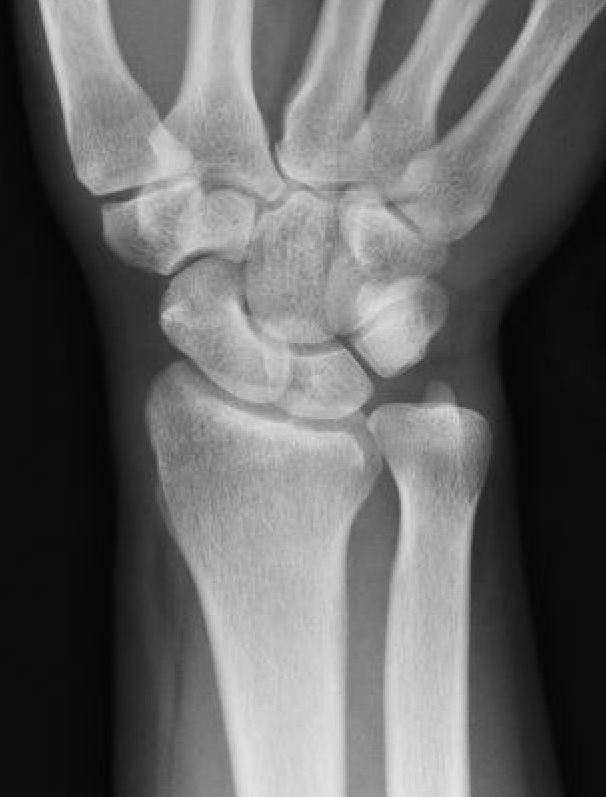

Ulna positive

Class 2 Degenerative TFCC tears

Central TFCC tear with ulna positive variance an ulnocarpal abutment on MRI

Background

Ulna impaction syndrome / Ulno-carpal abutment

Progression of wear

- TFCC thinning

- ulna head and lunate cartilage wear

- TFCC perforation

- lunate-triquetral ligament injury

- ulnocarpal osteoarthritis

Usually associated with ulna positive variance and treated with ulna shortening